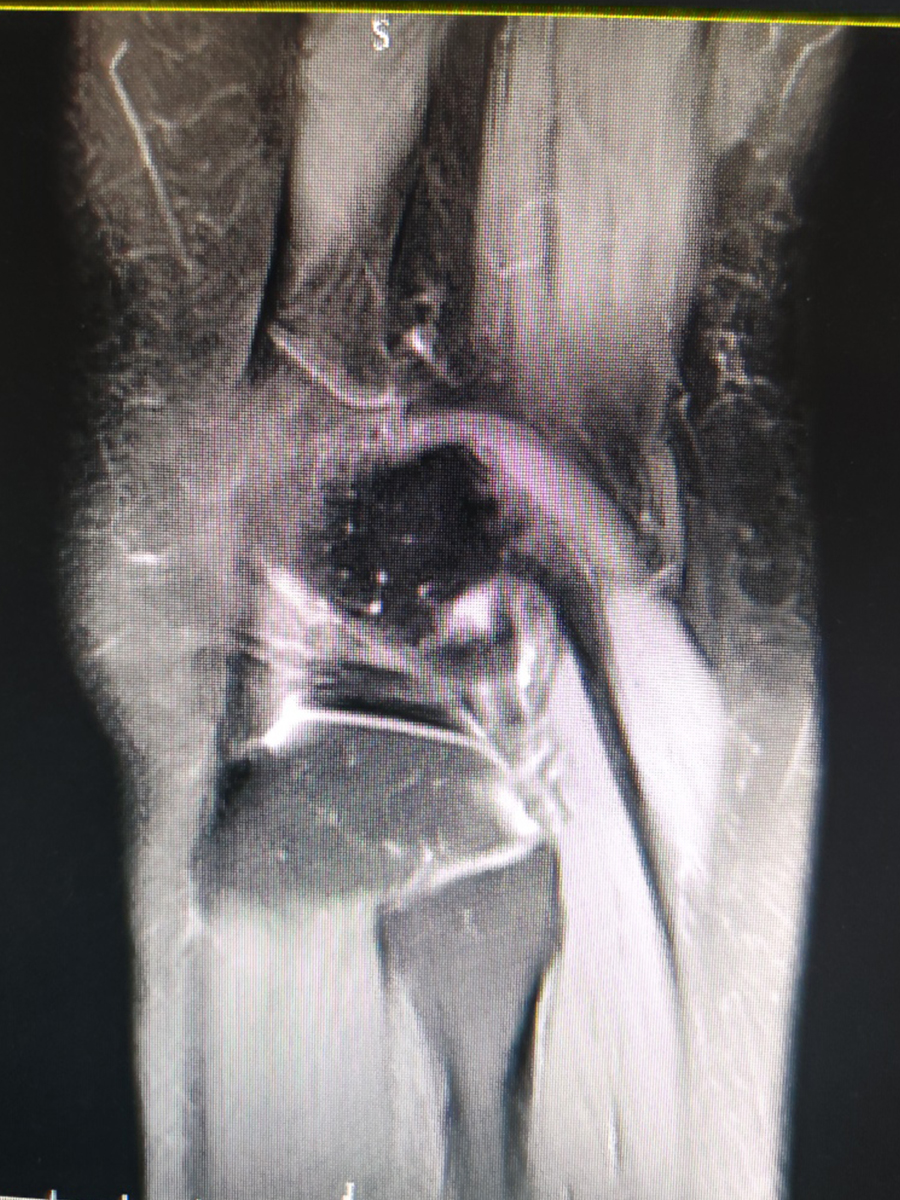

患者是一位中年女性,1个月前出现右膝疼痛,伴乏力,主要是下蹲起身时无力,疼痛以腘窝处为重,劳累后有加重迹象,休息后减轻,无肢体麻木。我给患者进行体格检查,发现右膝内侧压痛、肿胀,膝关节被动活动没有明显受限,承重屈膝60°受限,腘窝处可以触及肿块,大小1×2cm。嘱患者进行磁共振检查,提示关节积液和腘窝囊肿。综合其临床症状以及相关检查结构,以关节病收入我院,进行下一步治疗。